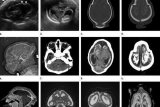

Zika telah menyebar secara cepat di Benua Amerika, sehingga mendorong Organisasi Kesehatan Dunia (WHO) untuk menyatakan darurat kesehatan internasional karena keterkaitan virus dengan penyakit mikrosefali.

Penyakit itu mengakibatkan bayi lahir dengan kepala berukuran kecil dan tidak normal, serta dapat menderita masalah perkembangan.

Zika telah dikaitkan dengan mikrosefali, sehingga para ilmuwan Yayasan Oswaldo Cruz menyarankan, agar perempuan hamil mengambil tindakan pencegahan khusus dan menghindari keramaian selama perayaan karnaval yang berlangsung di Brazil.